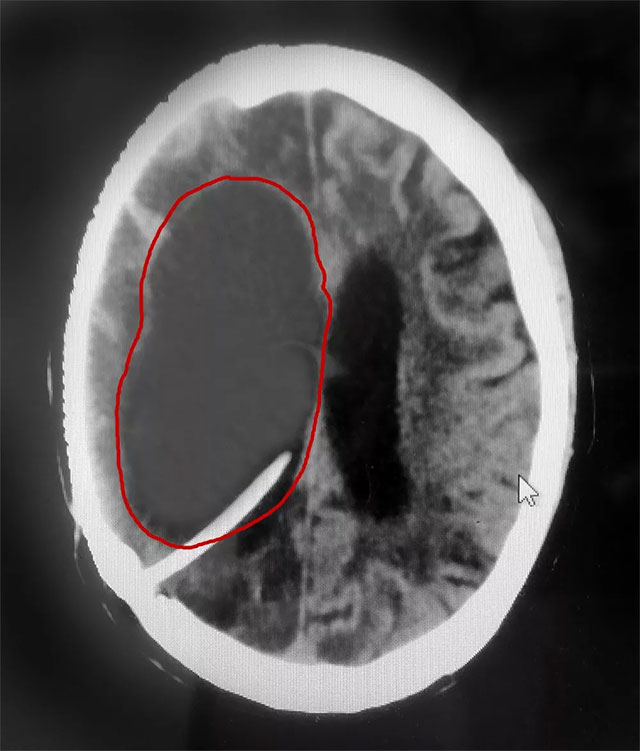

▲ 患者右侧脑室重度脑积水被及时置管分流

近日,上海蓝十字脑科医院神经外科6A病区收治了一位重度脑积水患者。三年前,患者金某(化名)因右侧大脑中动脉瘤破裂昏迷,在外院进行了开颅动脉瘤夹闭术和颅内血肿清除术。术后,由于伤口感染等原因,出现了脑脓肿、脑积水等并发症,长期处于昏迷状态。

在完善相关检查后,患者重度脑积水明确,若不及时治疗可能危及生命。

侯增欣主任团队经审慎会诊讨论,在排除患者手术禁忌症并获得家属同意的情况下,为金某实施了脑室腹腔分流手术。术中,侯增欣主任将脑室端引流管通过颅骨钻孔插入患者脑室内,引流管接上分流阀门以控制脑脊液流出速度,再连接腹腔端引流管,引流管经皮下隧道放置入腹腔。“这样一来,多余的脑脊液就可以由脑室通过引流管进入腹腔,由腹腔吸收,排除了患者脑部‘堰塞湖’的风险。”侯增欣主任表示。